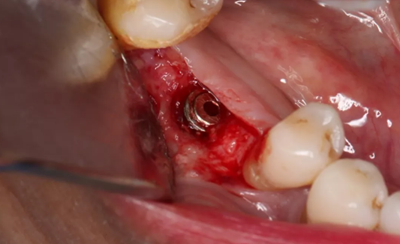

11、常規(guī)植入WEGO種植體一顆

牙槽嵴頂水平切口,翻瓣,牙槽嵴近中較遠(yuǎn)中豐滿。

(攝于2017年4月14日)

12、延期種植手術(shù)過程

使用直徑3mm的環(huán)形取骨鉆切取長約9mm的柱狀骨標(biāo)本,用于組織學(xué)和顯微影像檢查

由于取骨致窩洞較大,加之缺牙間隙大,只好選擇植入5mm直徑種植體;種植備洞完成后,頰側(cè)骨壁厚度僅約1mm。

植入國產(chǎn)威高(WEGO)5.0×11mm種植體,檢查種植體位于理想軸位。